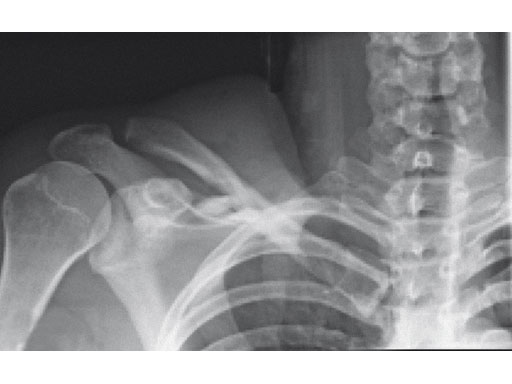

A 22-year-old man sustained an open clavicle fracture after a motorcycle injury.

Fig 1ab Preoperative x-rays.